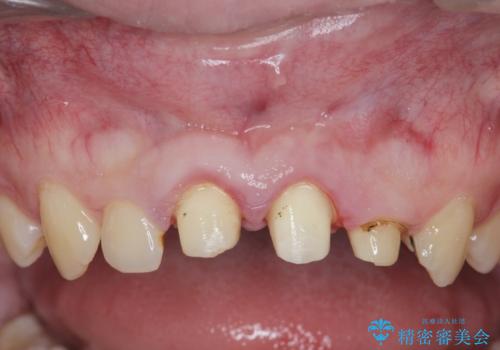

- 「前歯の見た目、歯ぐきの腫れを改善したい。」と希望され来院されました。

前歯には接着性の維持装置や、中途半端な形の連結クラウンが装着され、清掃性が悪く歯ぐきの腫れや、歯ぐきの形態の不揃いが認められました。